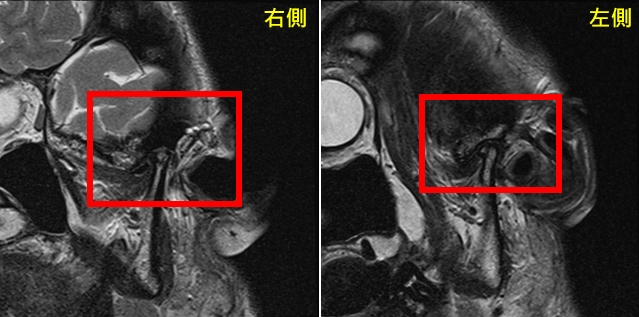

圖:治療前圖。曾小姐雙罹患側顳顎關節障礙症候群,出現肌筋膜疼痛症、關節盤不可復移位及骨關節炎。

圖:治療前圖。曾小姐雙罹患側顳顎關節障礙症候群,出現肌筋膜疼痛症、關節盤不可復移位及骨關節炎。

圖:治療前圖。曾小姐雙罹患側顳顎關節障礙症候群,出現肌筋膜疼痛症、關節盤不可復移位及骨關節炎。

圖:治療前圖。曾小姐雙罹患側顳顎關節障礙症候群,出現肌筋膜疼痛症、關節盤不可復移位及骨關節炎。經專業評估後,由口腔顎面外科呂明怡主治醫師施行關節腔玻尿酸注射,並由智慧賦能中心林志峰主任進行震波治療。透過跨專業協作,針對病因進行整體性處理,短短一個月內,曾小姐的顳顎關節疼痛、臉頰緊繃、喉嚨異物感及肩頸痠痛等症狀即大幅減輕。隨著持續治療,生活品質顯著提升,也逐漸找回自信與笑容。